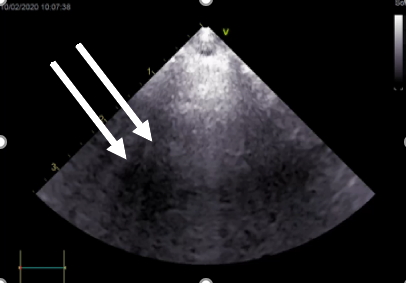

Lung ultrasound is more widely used in general practice and has the advantage of being carried out on the conscious patient. In the healthy patient, very little should be seen on ultrasound, but if there is fluid in the alveoli, B-lines may be seen (Figure 2). Ultrasound also allows for the identification of masses, and highlights if pleural effusion is present. It can then also be used to guide sampling or therapeutic thoracocentesis. Other types of imaging may be required, and sampling performed. Examples include thoracoscopy, rhinoscopy, bronchoscopy and bronchoalveolar lavage.

In the healthy patient, very little should be seen on ultrasound, but if there is fluid in the alveoli, B-lines may be seen